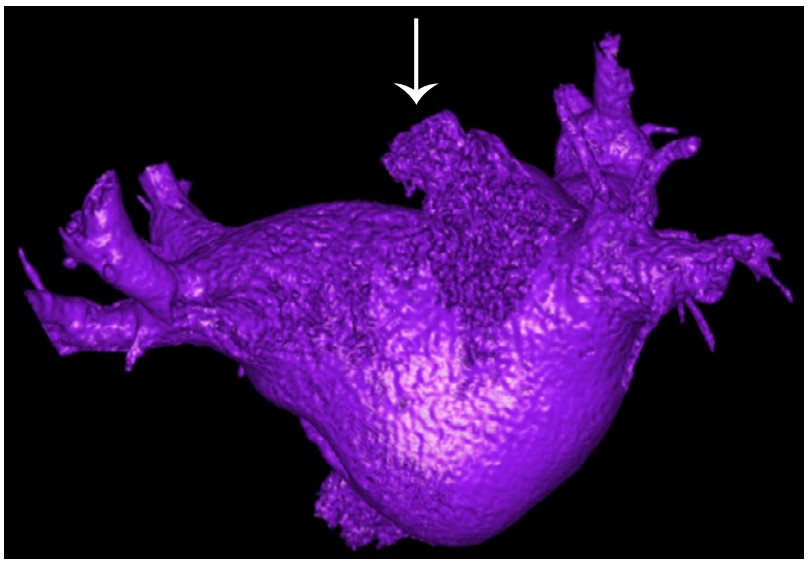

考虑患者发泡试验阳性,为排除房间隔分流,经食道超声心动图:左心房增大,左心房及左心耳内未探及明显团块回声,左心耳狭小,右心房正常,右心房及右心耳未探及明显团块回声,左心房与左侧肺静脉交通处膨大,房间隔未见异常分流。为进一步明确诊断,行左心房CT三维重建(肺静脉+左心耳)检查,半奇静脉曲张,纵隔及胃底多发曲张静脉,与左上腔静脉汇成一支,共同汇入左心房(近右上肺静脉汇入处),见图 2白色箭头。考虑患者永存左上腔静脉分流至左心房,导致反向栓塞脑梗死,联系心胸外科会诊后患者表示选择内科保守治疗。

| 图 2 患者左心房及肺静脉CT三维重建(白色箭头) |